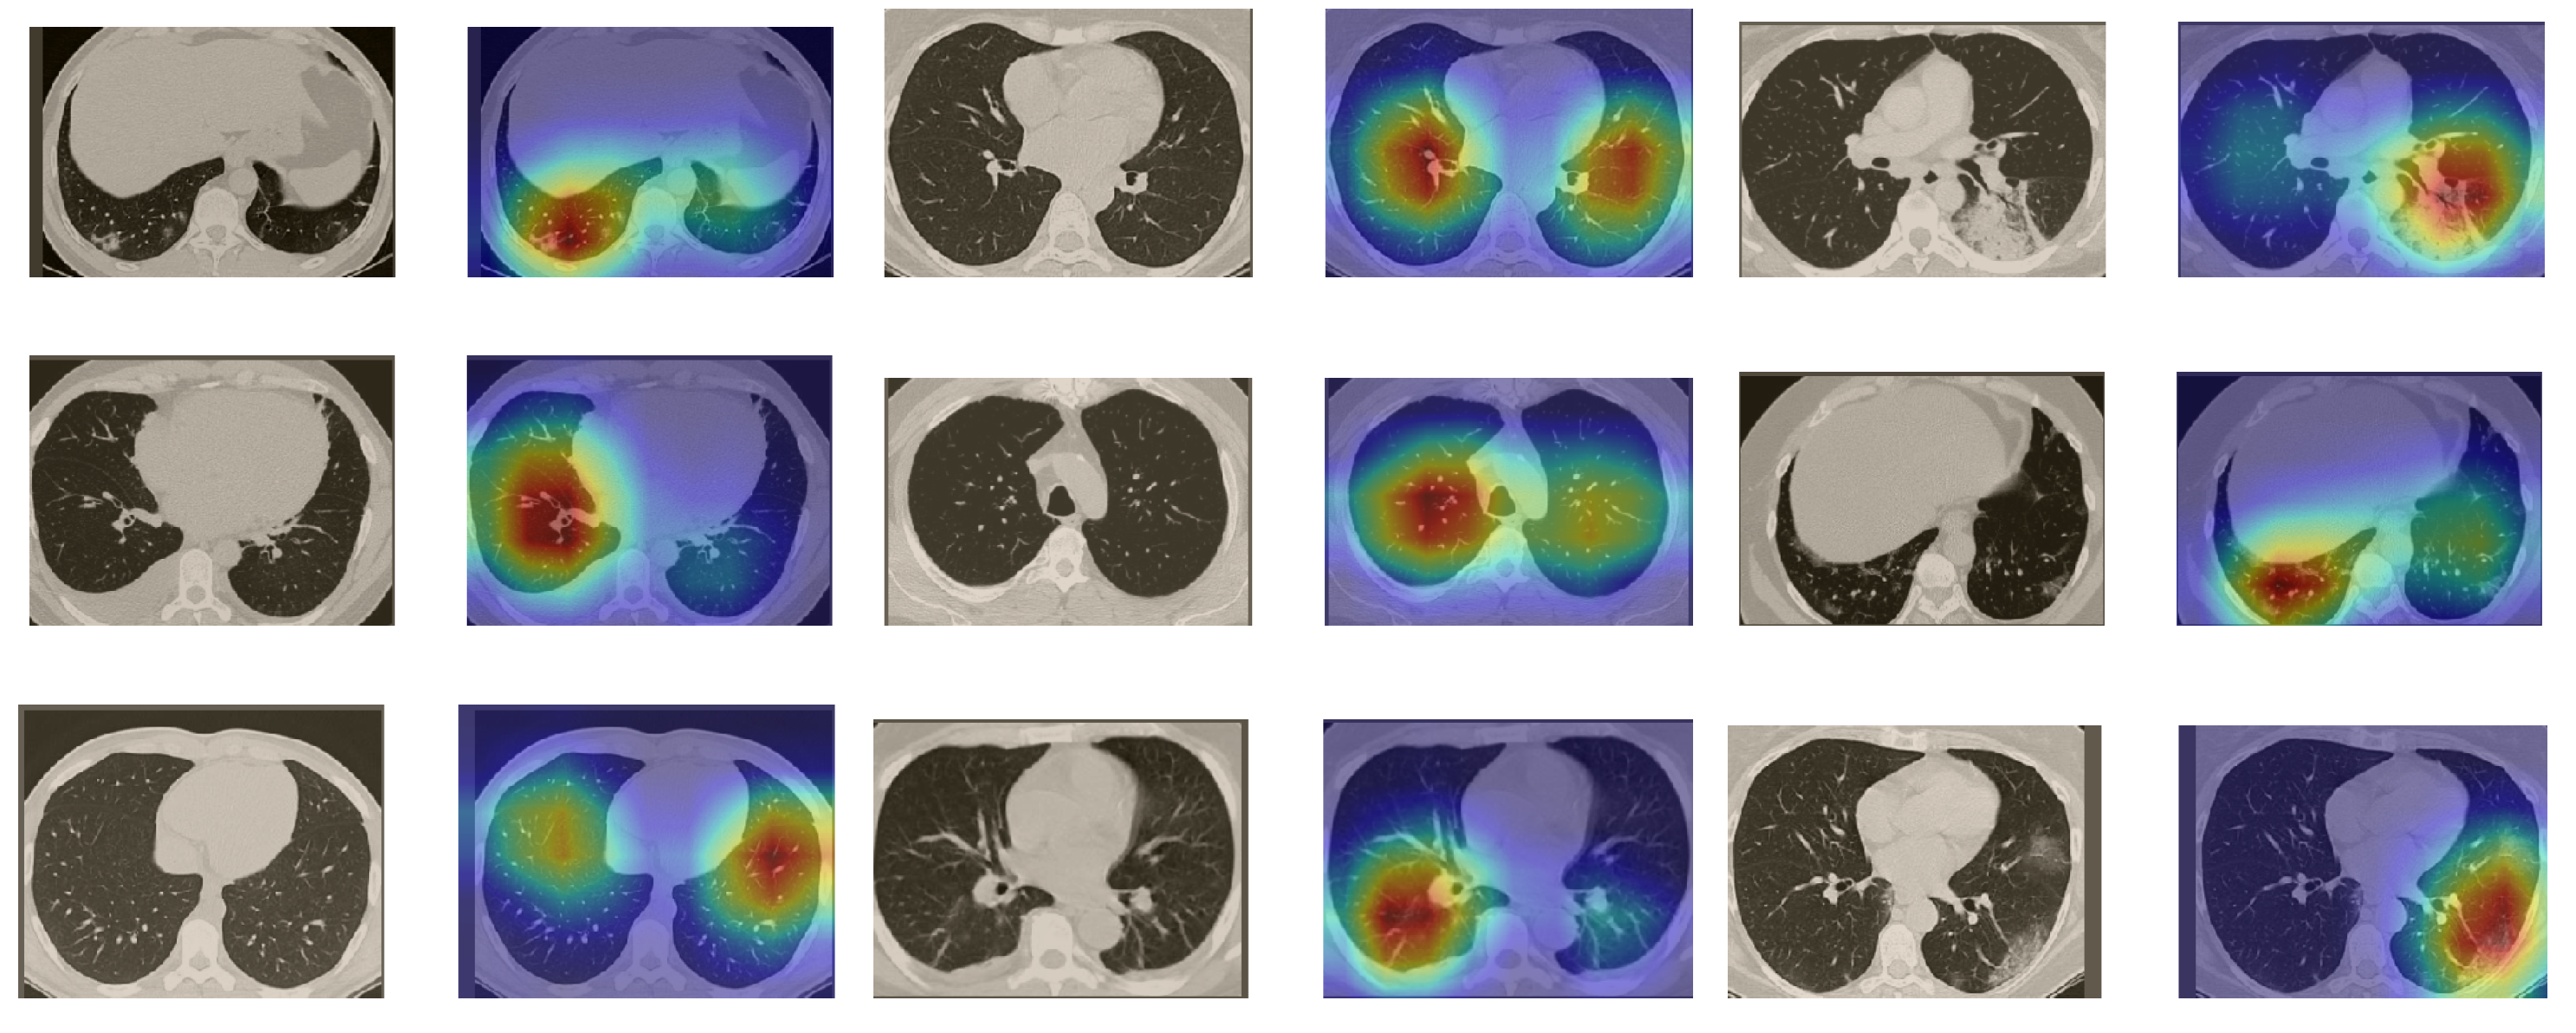

5.5.2. The Grad-CAM Visualization

In order to make our models more transparent and visually interpret the results, we provide the Grad-CAM localization maps generated by using different models. We utilized the CT images from COVID-19 class from the test set for each dataset, and highlight the important regions considered for the prediction. Figure 13 shows examples of CT images from the SARS-CoV-2 CT dataset and their localization maps. Interestingly, in most of the cases, our InceptionV3 model correctly classified them as COVID-19 cases and highlighted the regions of abnormalities in the CT scans, which are important for the model’s decision.

Figure 13.

Grad-CAM visualizations for examples of CT images from the SARS-CoV-2 dataset. Our InceptionV3 model correctly classified them as COVID-19 and localized the most relevant regions used for its decision. The first, third, and fifth columns show CT images with COVID-19 findings, whereas the second, fourth, and sixth columns represent their corresponding localization maps generated by Grad-CAM.

In a similar way, we considered classifying the test CT scans from the COVID-19 dataset by the DenseNet169 model, and highlight the important regions considered for predictions. We present samples of CT images and their localization maps in Figure 14. We can also see that our model is capable of detecting the COVID-19-related regions as annotated (small square in some images) by expert radiologists.

Figure 14.

Grad-CAM visualizations for sample CT images from the COVID19-CT dataset. Our DenseNet169 model correctly classified them as COVID-19 cases and highlighted the most relevant regions, as shown in the corresponding localization maps.